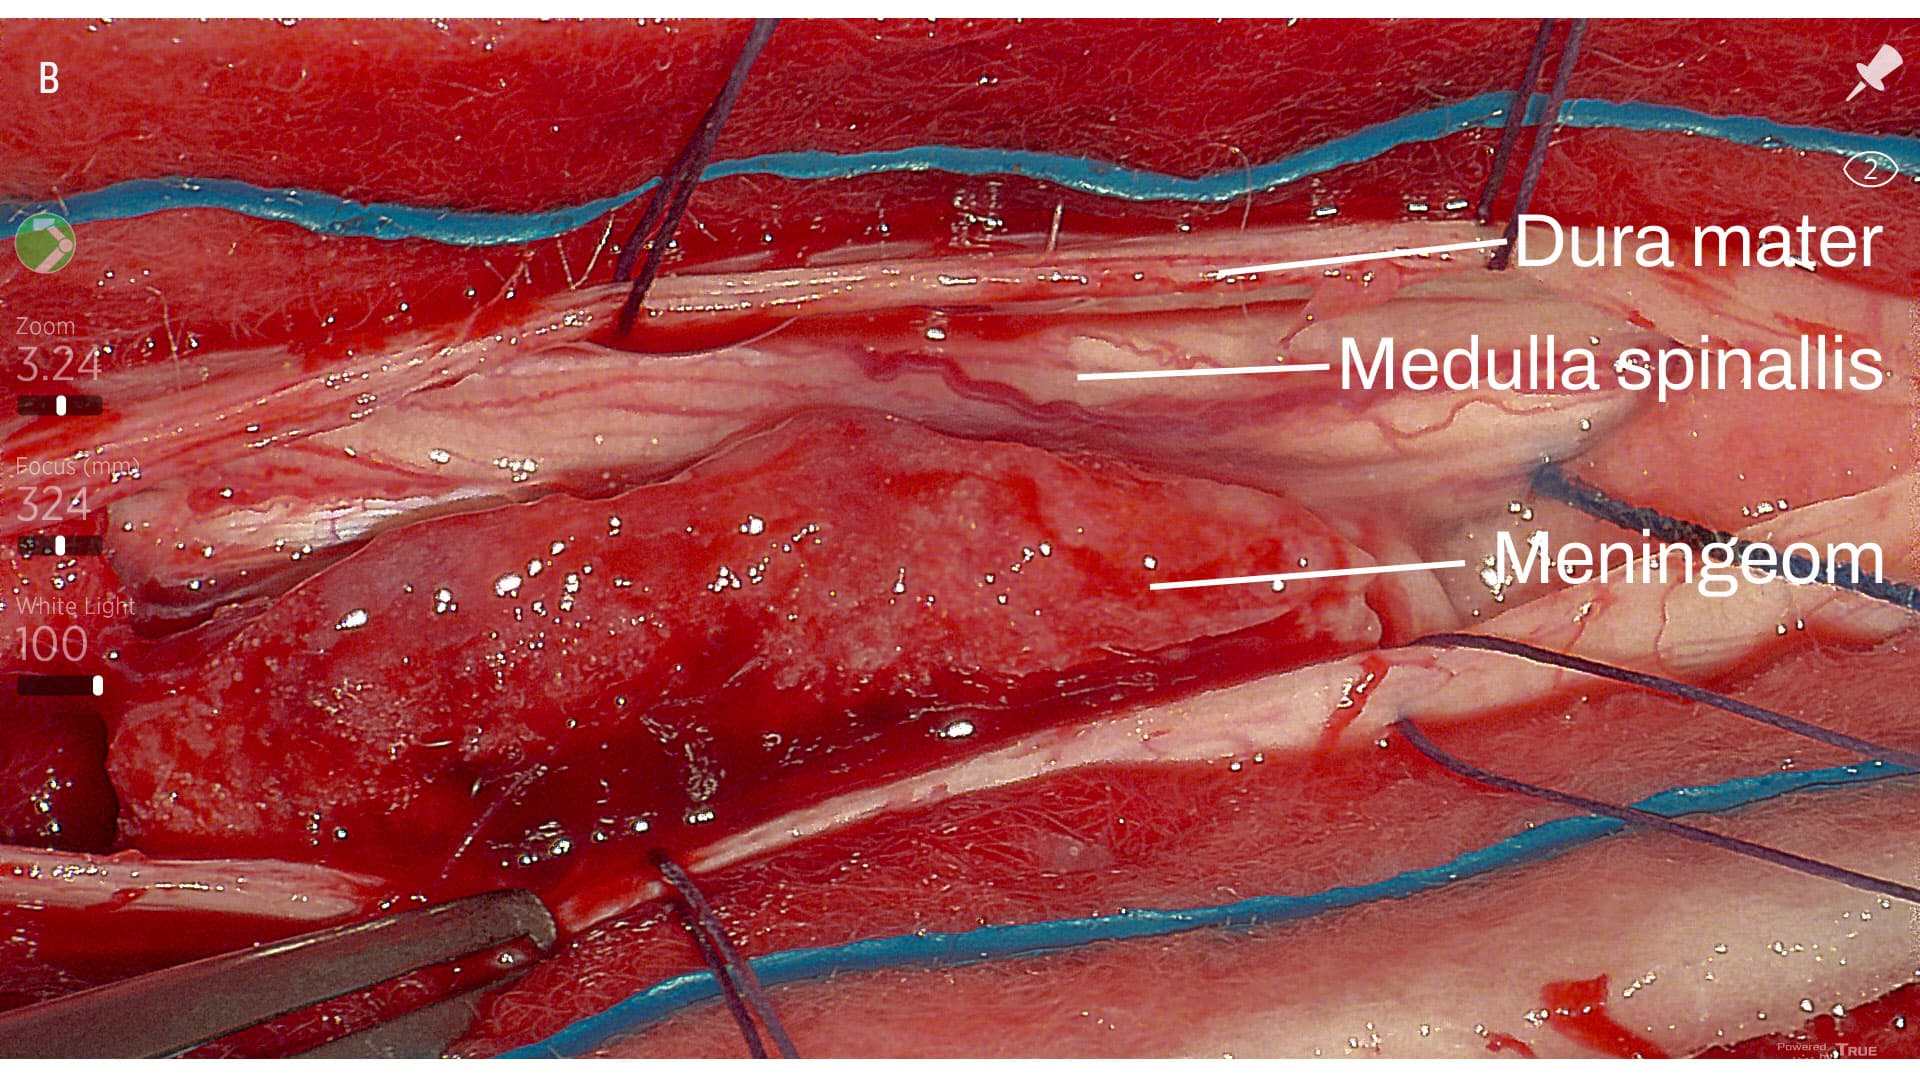

Tumoren blev makroradikalt fjernet under anvendelse af eksoskop (B). En peroperativ vurdering viste en hård, forkalket tumor, som blev fjernet in toto. Histologiske prøver viste et psammomatøst meningeom. Patienten havde et ukompliceret postoperativt forløb med let forbedring af underekstremitetsstyrken efter en måned.